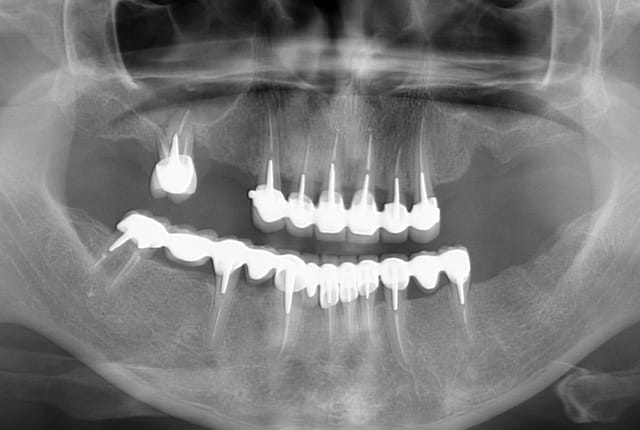

Patiente pas revenue depuis plus de 4 ans et demi.

Je l'ai vu début novembre pour un contrôle, et j'ai pu constaté qu'elle avait bien suivi mes conseils relatifs à l'HBD...

Rien n'a bougé, même les deux stellites sont impeccables!

Cela fait plaisir, le travail bien fait, durable, prévisible, peu importe qu'il s'agisse de biodentine ou d'endo-ic-couronne...

Pano 10022011 ujohsu - Eugenol

Pano 07112015 hvxbbe - Eugenol